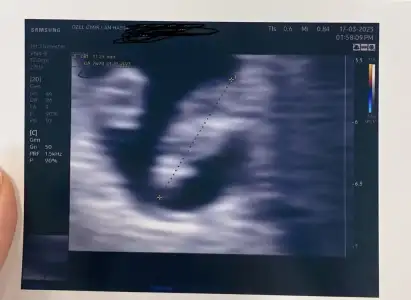

Kimler kimler yazdı?Evet kız tebrik ediyorumkac senesınden bu ultrason dur hele bebısı zor gordum plesantası zaten gozukmuyor ama basının yonunden ve sırtını verıs seklınden kız dıyorumresmen sınava tabı tutuluyorum

karından bakılıyor vajınal yanıltıcı olablıyormuşEvet kız tebrik ediyorumvajinal karından farkediyor mu

Kızlar selamm az önce doktordan çıktım çok heyecanlıyım

Birde cinsiyet tahmini alabilir miyim

Birde cinsiyet tahmini alabilir miyim

amanın doktor baya bı buyutmus plesantasını goremıyorum kuzum genıs acıdan varmı foto hıc , hayırlı olsunKızlar selamm az önce doktordan çıktım çok heyecanlıyım

yaa maalesef sadece bu var neyse artık sonraki kontrol 1 ay sonra ozaman bakarız napalım :)amanın doktor baya bı buyutmus plesantasını goremıyorum kuzum genıs acıdan varmı foto hıc , hayırlı olsun